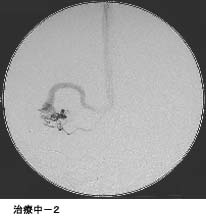

脳動静脈奇形に対する液体塞栓物質を用いた治療

治療により異常血管は閉塞されました。